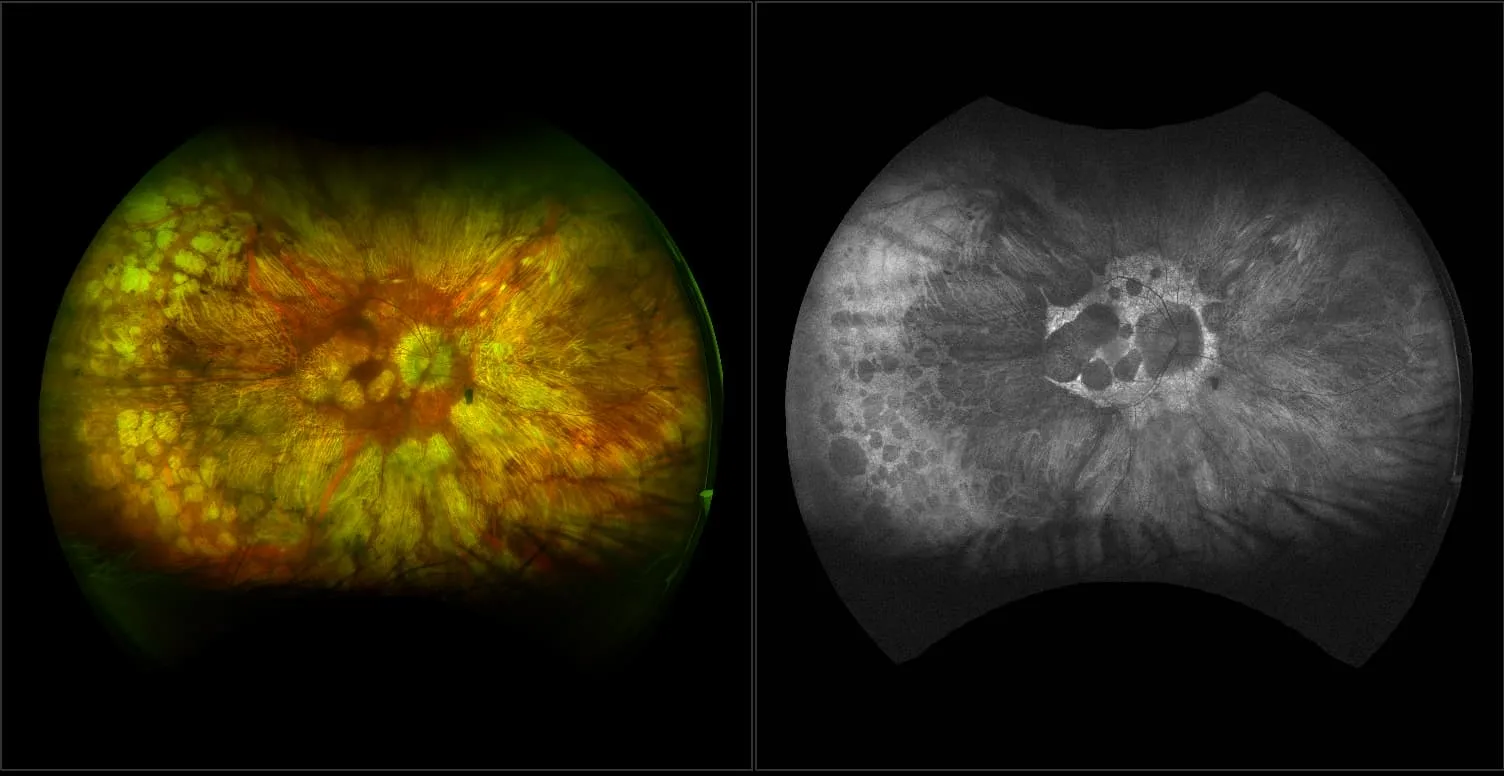

optomap images representing other retinal disease not found in common categories of pathology.